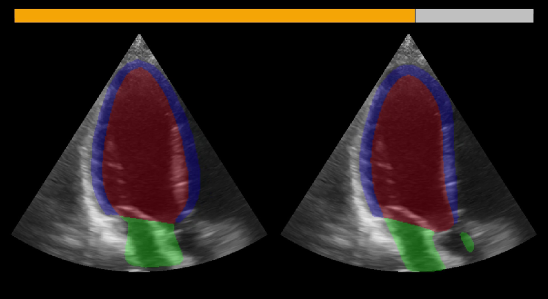

5 Real-time demo application

To demonstrate the potential of the inter-model agreement to detect out-of-distribution cases and faulty segmentations in real-time, a real-time application was created using the FAST framework [26]. It shows the segmentation output of the GCN and nnU-Net side by side together with a status bar that visualizes the agreement between the models. Fig. 10 shows a screenshot of the application in action. The demo video [27] shows the application in use while a clinician is operating a GE Vivid E95 scanner. The video demonstrates the effectiveness of the inter-model agreement as a method to detect out-of-distribution and low image quality cases. The video is available at https://doi.org/10.6084/m9.figshare.24230194.

Refer to caption

Figure 10: Screenshot of the real-time demo application. The GCN and nnU-Net segmentations are shown on the left and right side respectively. The color-coded status bar on top visualizes the agreement between the models.